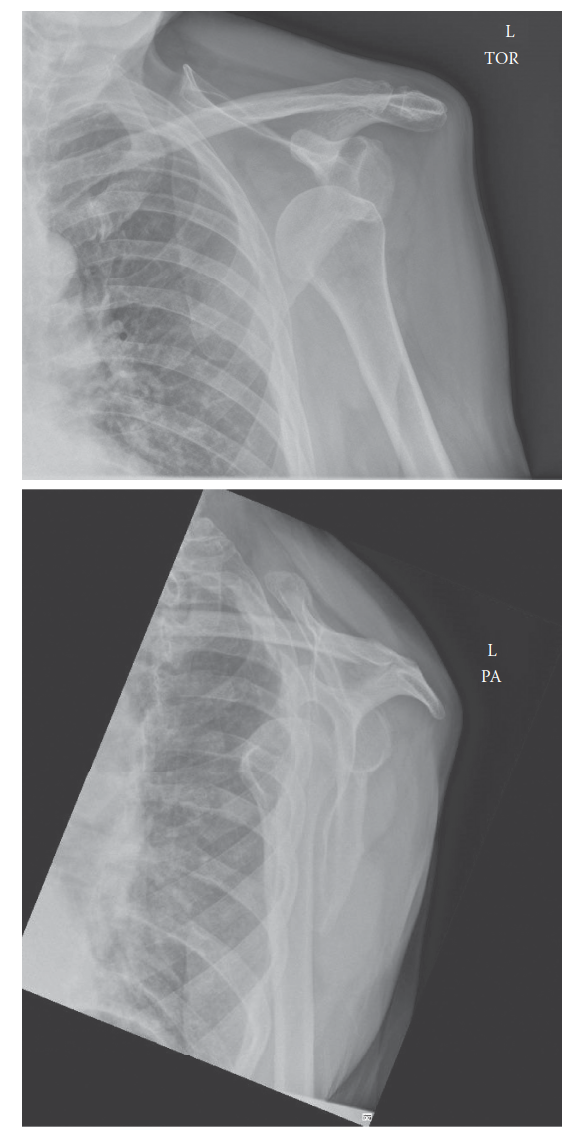

Management of Proximal Humerus Fracture 1. Describe these radiographs. Show Answer Show Explanation 2. How wo…

You are called to the emergency department to see a 60-year-old man who has fallen while running, injuring hi…

A 45-year-old man with epilepsy is brought to the emergency department following a sei- zure. He complains of…